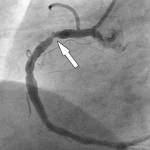

Что видит рентгенангиохирург

Врач устанавливает лучевую трубку в нескольких позициях. При этом пациента могут попросить задержать дыхание и не дышать, не двигаться, чтобы лучше получить изображение. Как делают снимки? Так как нужна детальная информация о всех сегментах коронарного русла, делается, как минимум две взаимно перпендикулярные проекции каждого участка. При этом важно, чтобы не было наложения изображений боковых ветвей. Для профилактики таких осложнений, как связанное с контрастом поражение почек, ишемия или нарушение ритма, избегают делать слишком много проекций, ограничивают разумными пределами время съемки. Подготовка, ход процедуры протоколируются врачом. В протоколе отражают и результаты обследования. Атеросклеротическая бляшка дает визуальный эффект песочных часов за счет нарушения заполнения контрастом сосуда.

При полной закупорке, ведущей, например, к инфаркту, ход артерии обрывается в виде пенька.